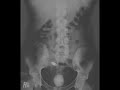

Bladder stone

This is a 35 year old male who presents with abdominal pain. He has a history of paraplegia following a motor vehicle collision. Frontal radiographs demonstrates a large calcification in the pelvis. The second frontal radiograph demonstrates a lamellated appearance of the calcification. Differential diagnosis for a calcification in the pelvis is broad and includes calcified uterine fibroids, pelvic phelobiliths in paraovarian veins, appendicoliths, bladder stones, atherosclerotic disease, and prostate calcifications. The large size of this calcification as well as the lamellated appearance is most consistent with a large bladder calculus. The most common causes of bladder calculi include a neurogenic bladder in the setting of paralysis as well as chronic bladder outlet obstruction.